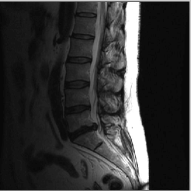

Spine 26.53 36.76 30.39 41.52 33.11 44.73

The reconstructions of an ankle image from its 4 fold Cartesian undersampled Fourier data, corrupted with zero mean complex Gaussian noise with a standard deviation σ=10𝜎10\sigma=10, are shown in Fig. 5. This is a really challenging case since the 1-D downsampling pattern is considerably less efficient than the 2-D random pattern used in the previous experiment. We observe that the non-local algorithm provides better reconstructions than the other schemes. Specifically, the TV scheme results in patchy artifacts. The DLMRI scheme results in blurring and loss of details close to the heel. The details are relatively better preserved close to the finger since there are no structures above or below it that aliases to it. By contrast to the classical algorithms, the degradation in performance of the non-local algorithm is comparatively small. The quantitative comparisons of the algorithms on this setting using different images are shown in the top section of Table IV.

Refer to caption

(b) Spine

(f) NLS,SNR=29.43

Figure 7: Comparison of different MR images using NLS algorithms in the presence of noise. We consider the recovery from a three fold undersampled radial sampling pattern, contaminated by zero mean complex Gaussian noise with standard deviation σ=10𝜎10\sigma=10. The top two rows show the original and reconstructed images, while the error images scale by a factor of five are shown in the bottom row. We observe that the NLS scheme preserves well the edges and the fine details at low acceleration with presence of noise.